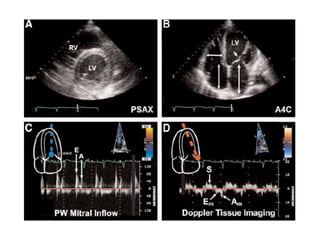

Mitral inflow profiles in impaired

diastolic dysfunction in dilated

cardiomyopathy.

Reversal of E/A ratio with prolonged

deceleration time more than 200ms

Mitral inflow profilesin impaired diastolic dysfunction in dilated cardiomyopathy. Reversal of E/A ratio with prolonged deceleration time more than 200ms